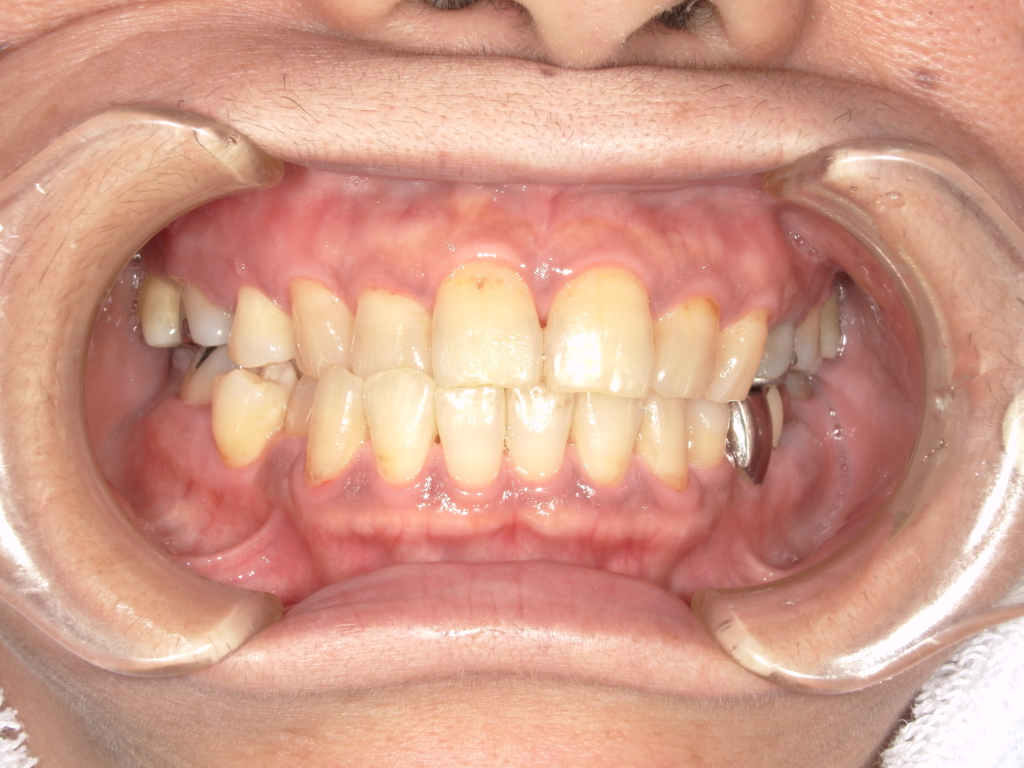

Y様インプラント実例 #44

左の上下の奥歯をインプラントで治療しています。

左下の奥歯は歯を抜くのと同時にインプラントの埋め込みを行っています。

被せものは上下、セラミックスで作っています。

治療前

治療後